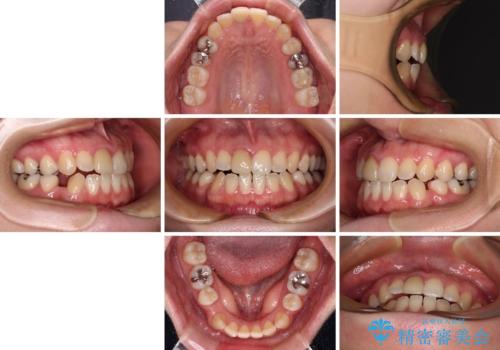

【モニター】後戻りでできた隙間 ワイヤー装置での再矯正

- 学生時代に行った抜歯矯正の後戻りで、隙間ができてしまったことを気にして来院された患者様です。

マウスピース矯正を検討されていましたが、後戻りの隙間が非常に大きく、奥歯を前方に移動させる必要があるため、ワイヤー装置にて矯正治療を行うこととしました。

舌の突出癖が非常に強く、その影響で隙間ができてしまったので、舌のトレーニングをしっかりと行っていただきました。

上顎歯列は歯の移動量が少なかったため、セラミッククラウンは装置を装着せずに治療を終えることができました。